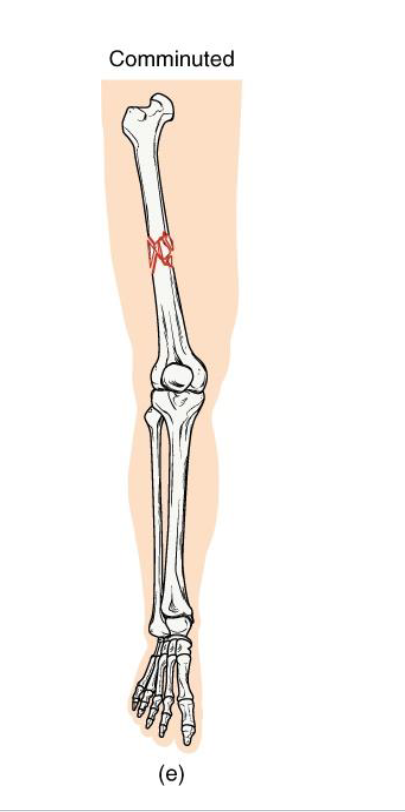

Comminuted Fracture

Definition: Bone is shattered into three or more fragments.

Mechanism: high impact trauma (ex: car accidents, falls from height)

Clinical note: Complex repair; may require surgical plates/pins; slow healing.

Key concept: represents severe energy transfer → bone fragmentation

<p><strong>Definition: Bone is shattered into three or more fragments.</strong></p><p><strong>Mechanism: high impact trauma</strong> (ex: car accidents, falls from height)</p><p><strong>Clinical note:</strong> Complex repair; may require surgical plates/pins; slow healing.</p><p><strong>Key concept: represents severe energy transfer </strong>→ bone fragmentation</p>